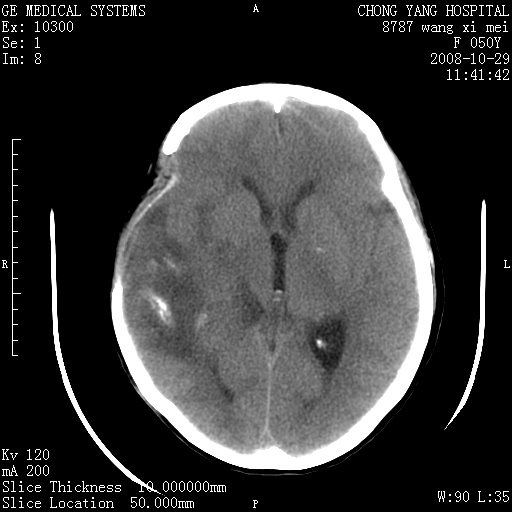

标题: CT16469:女,50岁,胶质瘤术后6年,今平扫加增强,请大家帮 [打印本页]

标题: CT16469:女,50岁,胶质瘤术后6年,今平扫加增强,请大家帮

右侧颞顶部可见低密度实变影,内见不规则钙化灶,边界不清,占位效应明显,侧脑室后角受压移位,符合胶质瘤术后复发改变。

右颞骨局限性缺如,局部脑组织无外隆。右颞叶可见片状脑脊液样低密度影,边缘较清,右侧侧脑室三角区可见一块状等密度影,且伴有强化,余未见明显异常改变。

考虑:右大脑术后改变伴肿瘤复发。

考虑右侧颞顶叶胶质瘤术后复发。

应考虑肿瘤复发,右颞顶叶已出现轻度强化肿块.必要时可与原片比较以下.

右侧颞顶部混杂密度影,内有钙化,有占位效应。应该是复发灶。结合术后片更好。

胶质瘤是易复发的,这个病人有复发灶